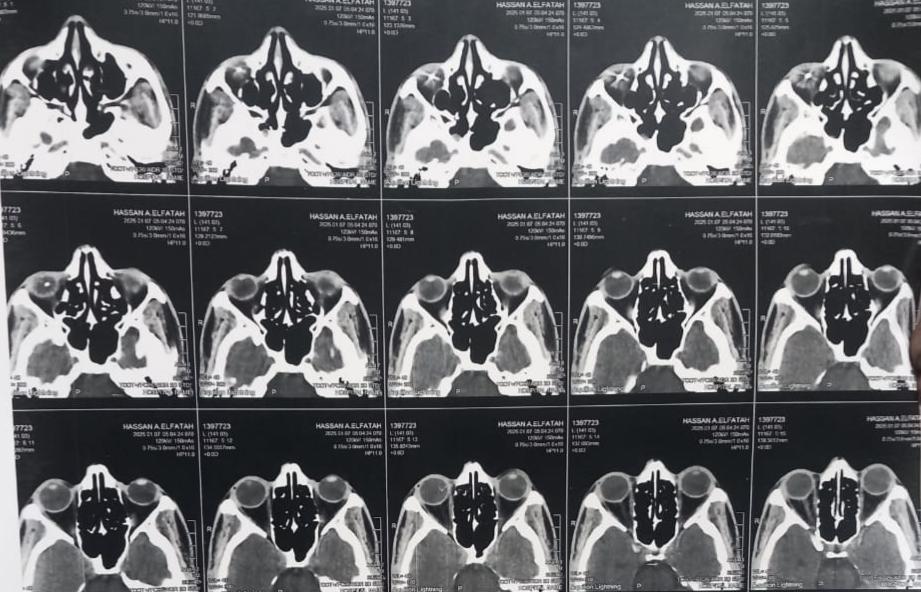

كان قسم طب وجراحة العيون بالمستشفى الرئيسي قد استقبل شاب من أسنا بمحافظة الأقصر، يبلغ من العمر ٣٥ عاما، أصيب بانفجار مقلة العين وجرح بالصلبة، ومياه بيضاء إصابية، وذلك نتيجة إصابته أثناء العمل وتطاير أجزاء من جسم معدني، ليستقر داخل العين، ويسبب نزيف بالجسم الزجاجي وإلتهابات داخل العين واشتباه انفصال شبكيه العين.

و قام الفريق الطبي بإجراء إصلاح لجرح بصلبة العين وإزالة المياه البيضاء بالموجات فوق الصوتية وزرع عدسة رخوه ، وتمت عملية إزالة الجسم الزجاجي واستخراج الجسم المعدني الصلب من داخل العين، مع الحفاظ على قدرة المريض الشاب على  الإبصار.